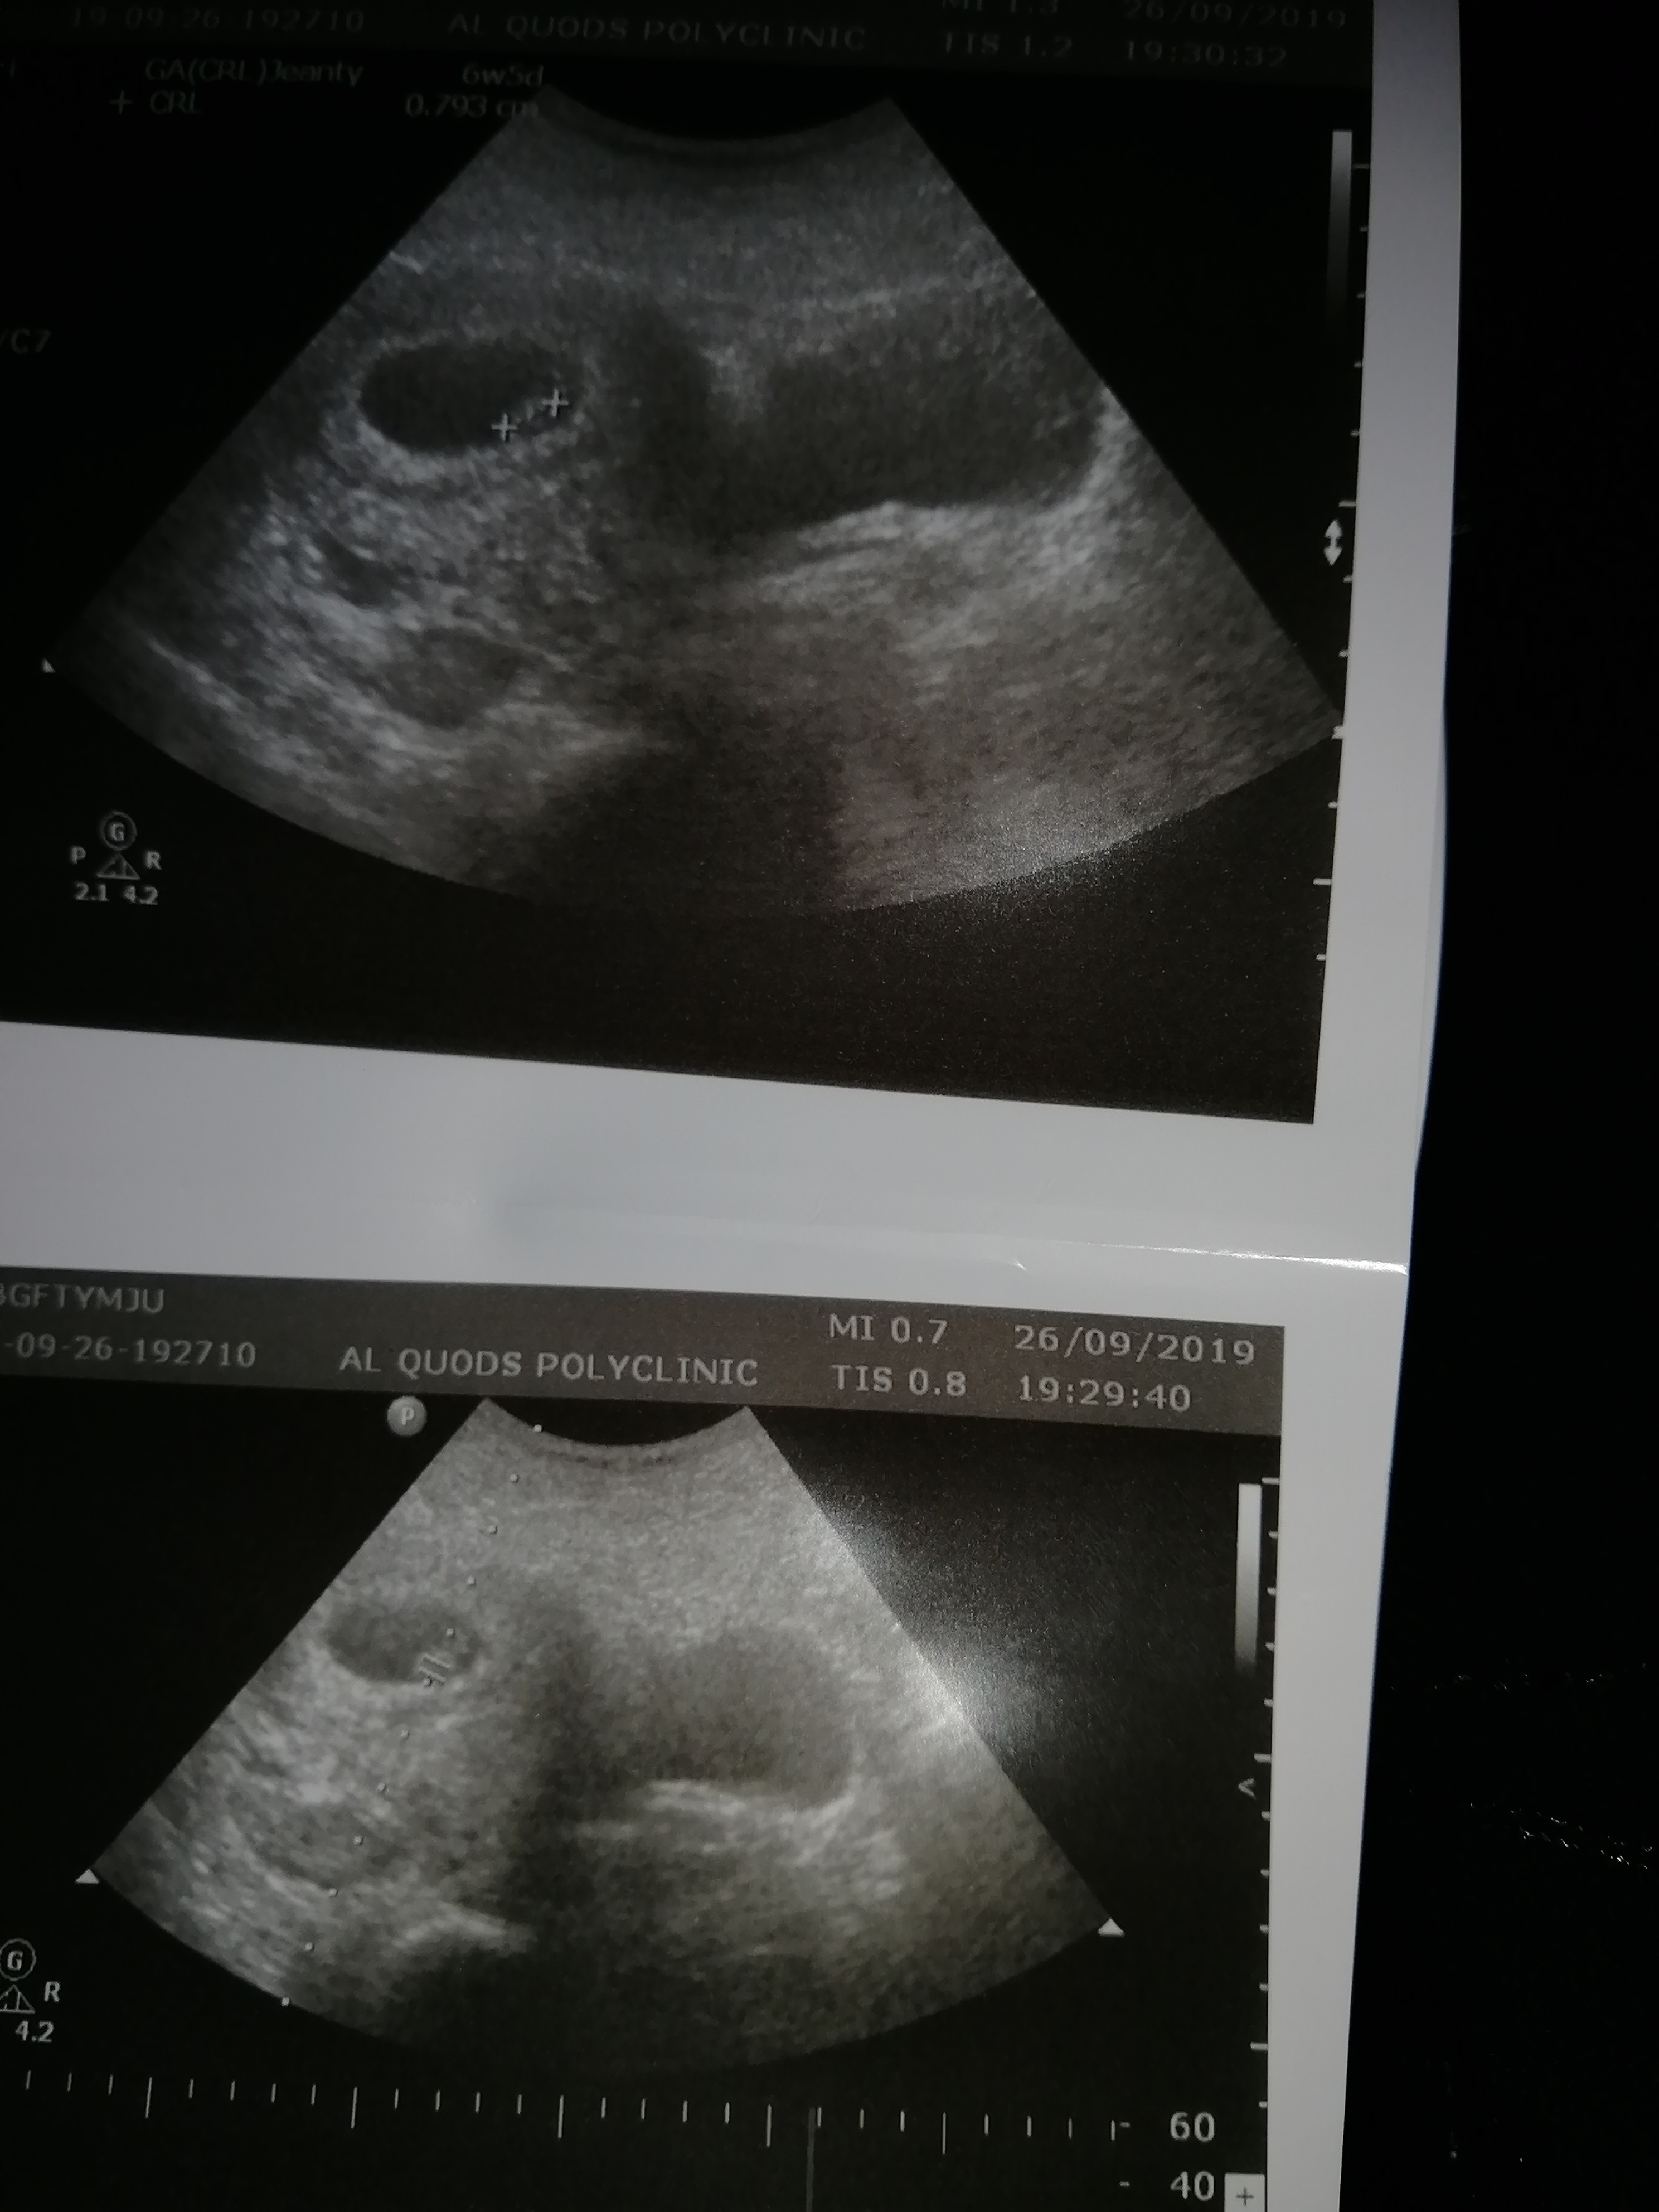

I have been reading up on the ramzi theory and wondered what you all thought of my abdominal scan taken at 6 weeks?:think: